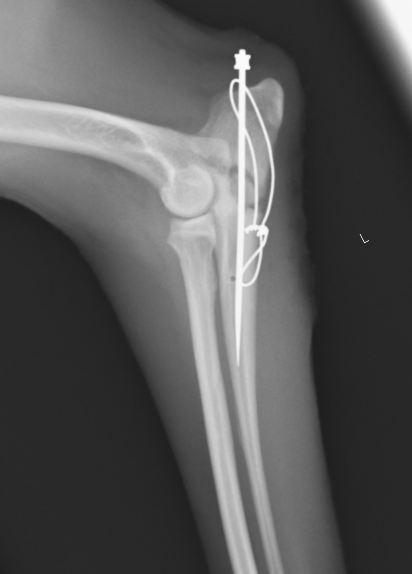

術後のレントゲン画像です。骨折線があい、向きが揃っているのがわかります。しかし、受傷から時間が経っているため骨折線をピッタリと合わせることは困難です。

術後は1ヶ月半〜2ヶ月くらいで抜ピンとなります。また、関節をまたいだ骨折であったため、長期的にみると関節炎が進行していく可能性があるため、長い経過観察が必要となります。